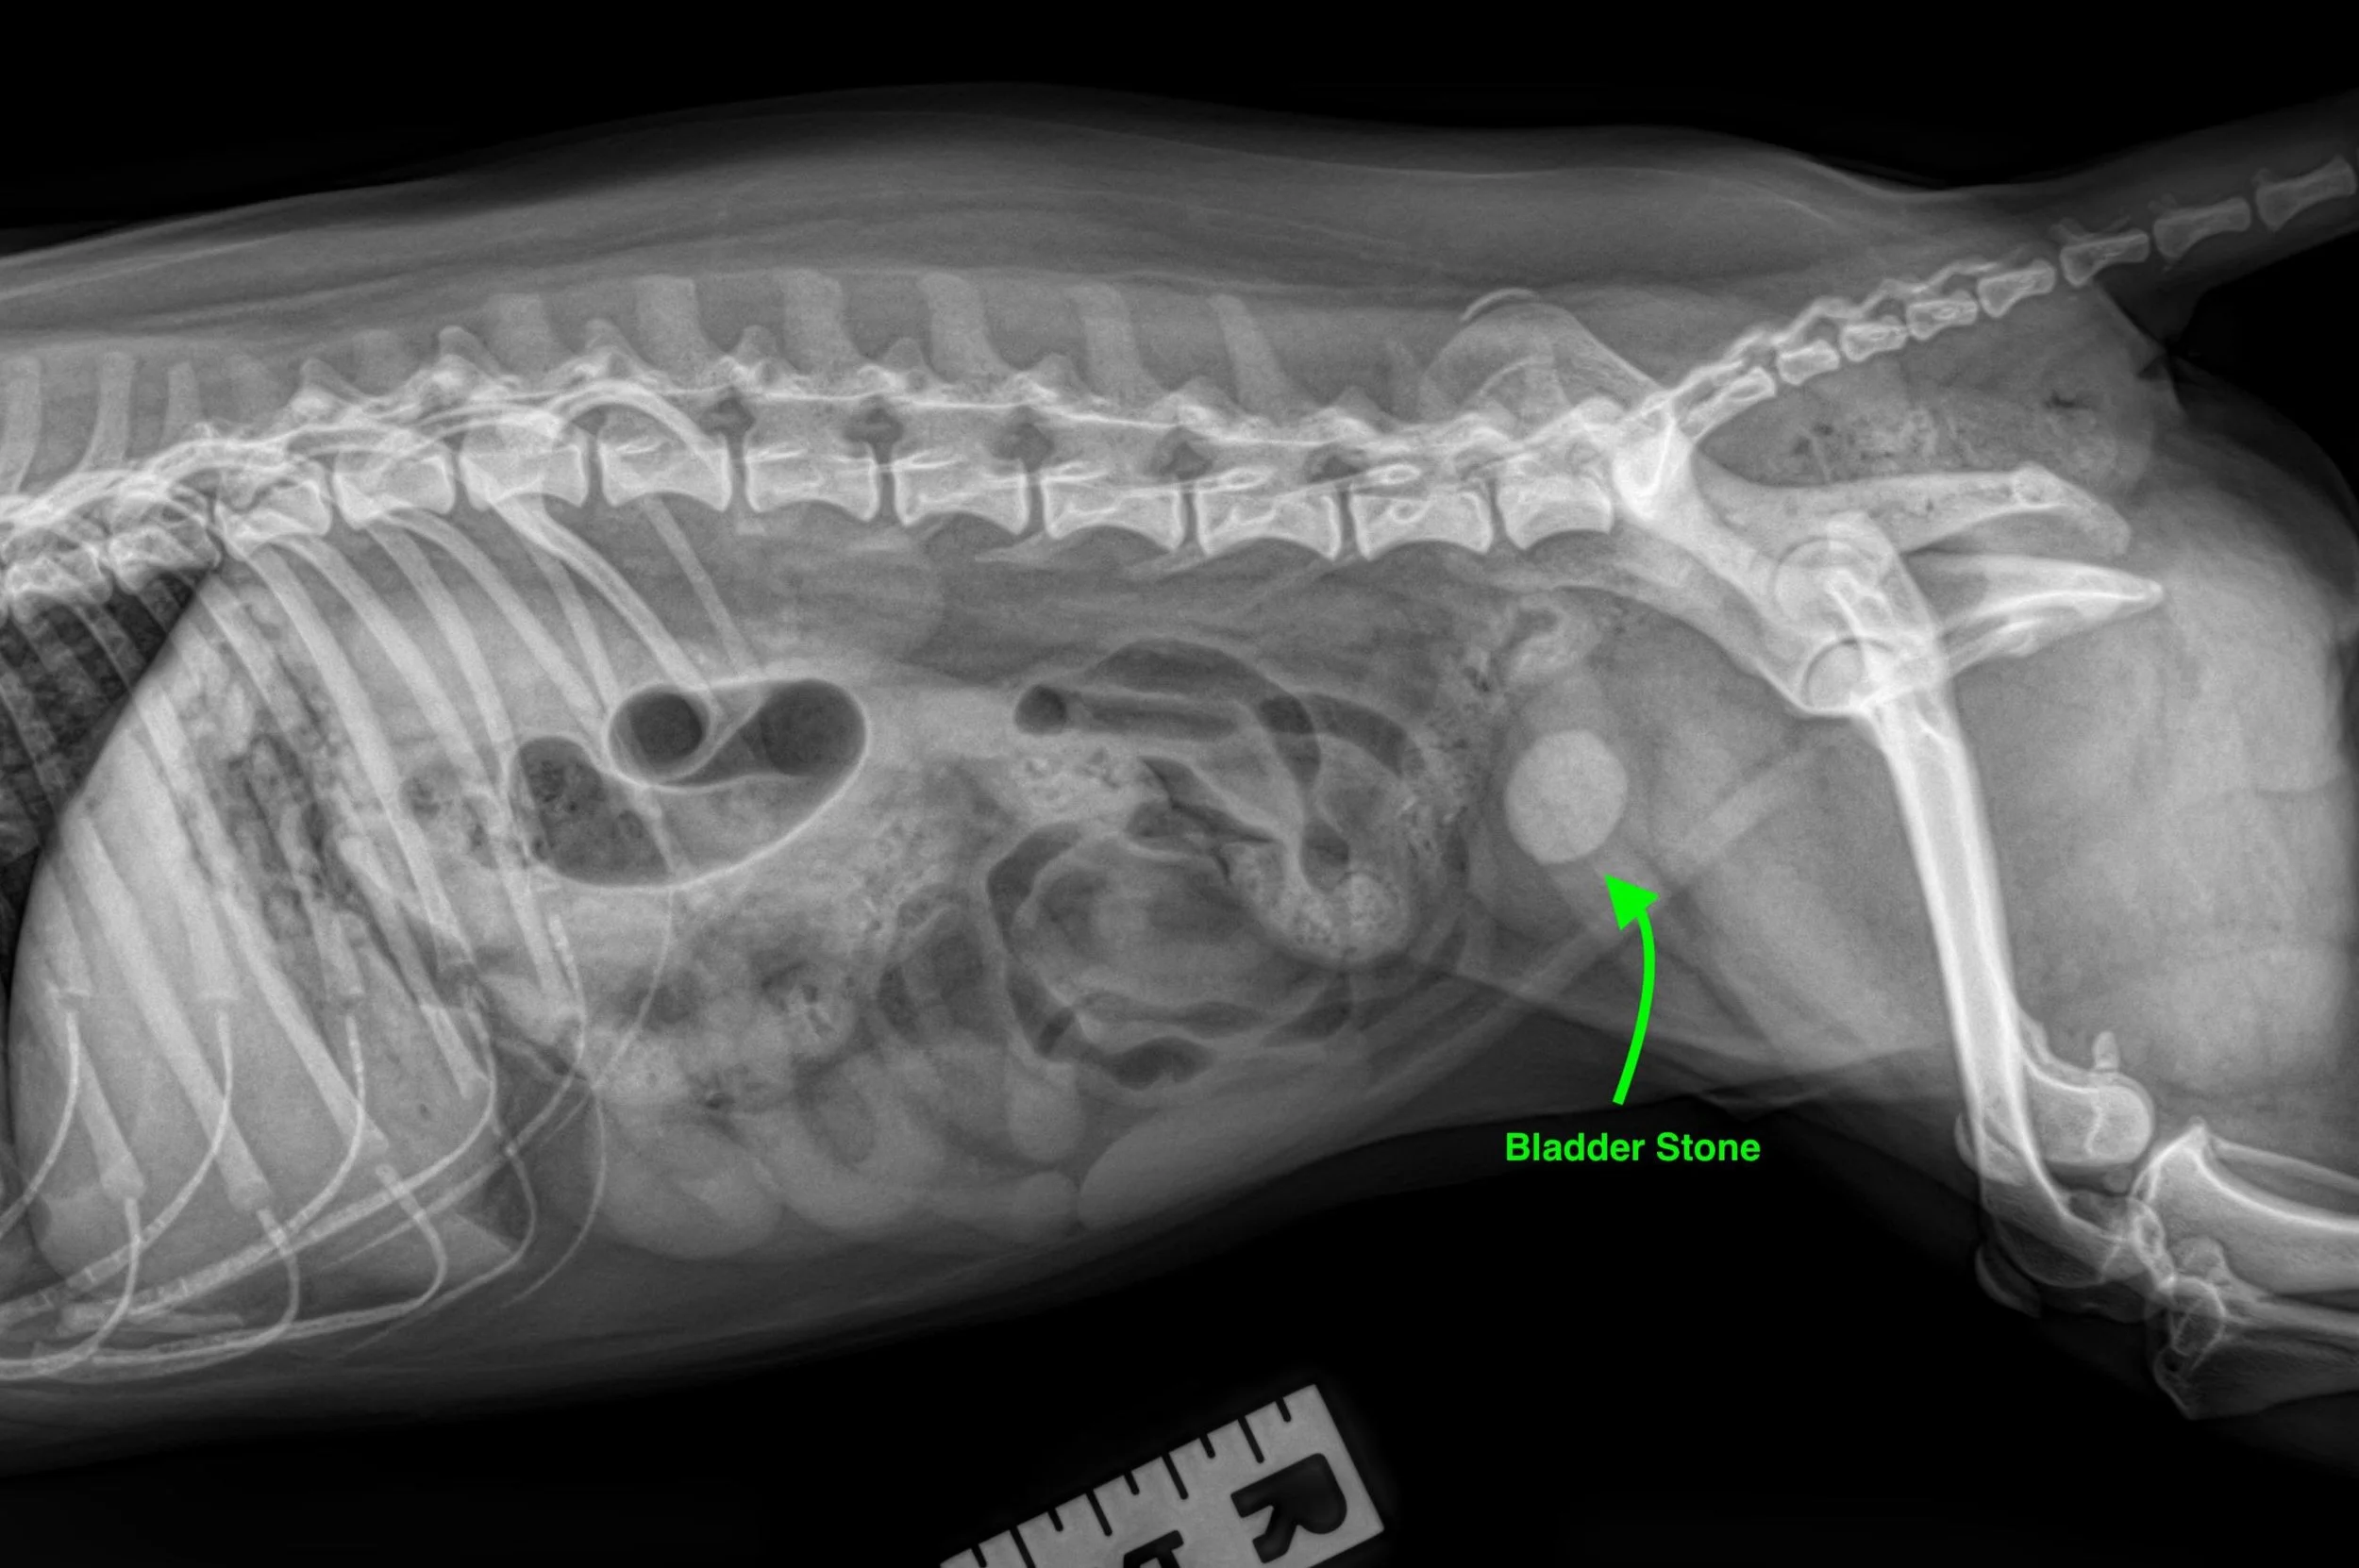

Some large stones can be felt on physical examination; however, most pets need to have an x-ray or ultrasound of the bladder to see the stone. A urinalysis and culture of the urine are often performed to determine the crystal type of stone and other related concerns. After removal, the stones will be sent for mineral analysis.

Certain types of stones (struvite) can be dissolved by feeding veterinary prescription foods; however, many stones require surgery for removal. The surgical procedure to remove bladder stones is called a cystotomy. During a cystotomy, the bladder is opened and the stones removed. The bladder and urethra are flushed during the procedure to ensure complete removal of all stones. After the procedure, a radiograph or ultrasound is performed to verify complete removal of all of the stones.